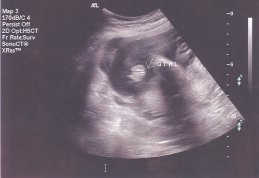

Улыбка писал(а): Аничка, спасибо еще раз, зая! Время так быстро бежит! Даже не верится, что у тебя уже 33 недели!!! Ой Улыбка и не говори.Мне чем ближе срок тем страшнее становится.Больше всего боюсь как моя 2-х летка дочка к братику отнесётся,чувствую 5 точкой ревновать будет по страшному.Она уже как обезьянка на мне в последнее время виснет,везде по пятам да и на ручки просится постоянно.Не было такого у нас раньше,прям как чувствует что ли. Смотри я кстате фотку с дочкиного УЗИ откопала,почти такой же ракурс,ПИРОЖОЧЕК

| Вложения: |

scan0001.jpg [ 16.08 КБ | Просмотров: 1294 ]

anichka писал(а): Смотри я кстате фотку с дочкиного УЗИ откопала,почти такой же ракурс,ПИРОЖОЧЕК  Возможно, что в таком же ракурсе у мальчика будет тоже пирожочек  , но он будет другой, эта полосочка, которая проходит посередине пирожочка будет белая , а у девочек она черная между двух беленьких (думаю понятно объяснила  ).